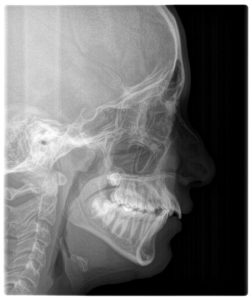

A combination of clinical evaluation, radiographs, and functional tests revealed that it was both anatomical and habitual — a dual problem.

- Mild enlargement of adenoids causing partial obstruction

- Narrow palate and open bite

Follow-up imaging and ENT review showed that the adenoids had reduced naturally.